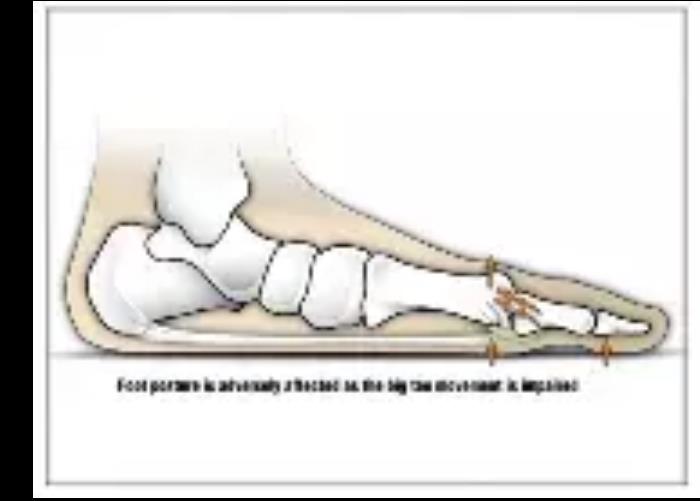

推蹬运动需要足部形成一个刚性杠杆,大拇趾作为支点,足跟抬起,支撑身体重量。

而扁平足的足部关节是旋前,旋前是足部关节活动度最大的,所以扁平足无法有效稳定足部,足部推蹬的时候,大拇趾“杠杆”效率下降,关节运动力学改变,拇趾形态向外翻。